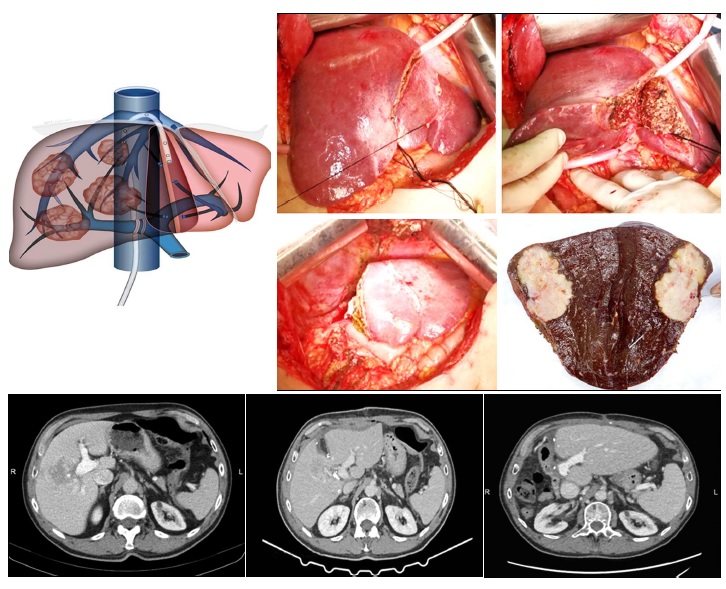

In these patients, we proposed a new technical variant of ALPPS, called parenchyma sparing ALPPS, consisting in shifting the transection plane though segment 4 (instead of the falciform ligament), thus increasing the FLR (2). The transection plane was established and performed under guidance of intraoperative ultrasound, ensuring oncological margins while maximizing the remnant liver volume.

- Preserving the left part of S4; - Partial transection through S4 using IOUS guidance; - (Right) portal vein ligation with minimal hilum dissection; - Partial (right) liver venous deprivation - right accessory veins sectioned-ligated; - Longer interstage interval (2-3 weeks); - Extra-glissonian approach during staged 2.

- Feasible even when ALPPS is not (S2-3 volume is <15%); - Safer than ALPPS: eliminates ischemia of segment 4, avoids biliary fistula due to segment 4 exclusion, and reduces the risk of liver failure due to small FLR.

We present the case of a 78-year-old male patient with significant comorbidities (atrial fibrillation, grade II hypertension, moderate pulmonary hypertension, compensated heart insufficiency, dyslipidemia), diagnosed at contrast MRI and CT with a tumor located in segments 5-8 liver lesion with extension to segments 6, 7, 4 and 1, in contact with the middle hepatic vein, enclosing the anterior right portal pedicle and in contact with the posterior right and the right portal pedicles (see video). The percutaneous tumor biopsy showed a moderate differentiated intrahepatic cholangiocarcinoma.

The patient required and extended right hepatectomy. However, the volumetry of segment 2 and 3 was insufficient even for a standard ALPPS, with parenchymal transection in the plane of the falciform ligament. Therefore, our new variant of ALPPS, parenchyma sparing ALPPS, was deployed, adding to the future remnant liver (FLR) part of segment 4 (see video). In this setting, the preoperative FLR was 24.8%, that increased to 34% during the interstage interval. No intraoperative adverse events were encountered during both operations. During the interstage interval of 15 days, there was a minor bleeding exteriorized through the drain placed on the cut surface, conservatively treated, requiring transfusion (1 unit). After the second stage, the postoperative course was uneventful, and the patient was discharged on the POD 8. The patient was alive and disease-free at 18 months.